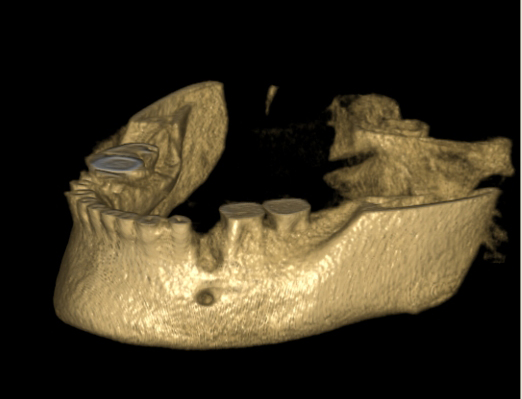

Jedná se o augmentační metodu při dostavbách kosti a defektech kosti horní a dolní čelisti.

Nový typ kortikální laminy (OsteoBiol) slouží k překrytí augmentačního materiálu při rozsáhlých 3D augmentacích a u velkých kostních

defektů. Jedná se o bovinní typ kortikální kosti.